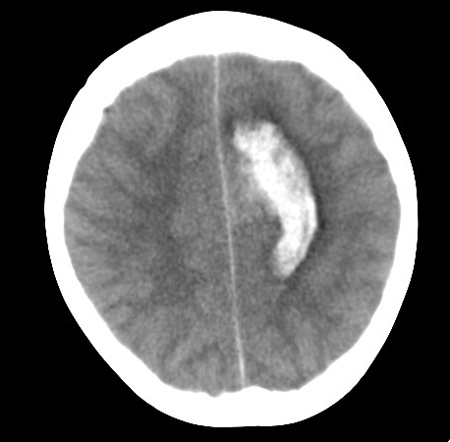

Left posterior frontal intracerebral haematoma secondary to ruptured arteriovenous malformation (axial unenhanced computed tomography scan)

From the collection of Mr R. J. Edwards; used with permission